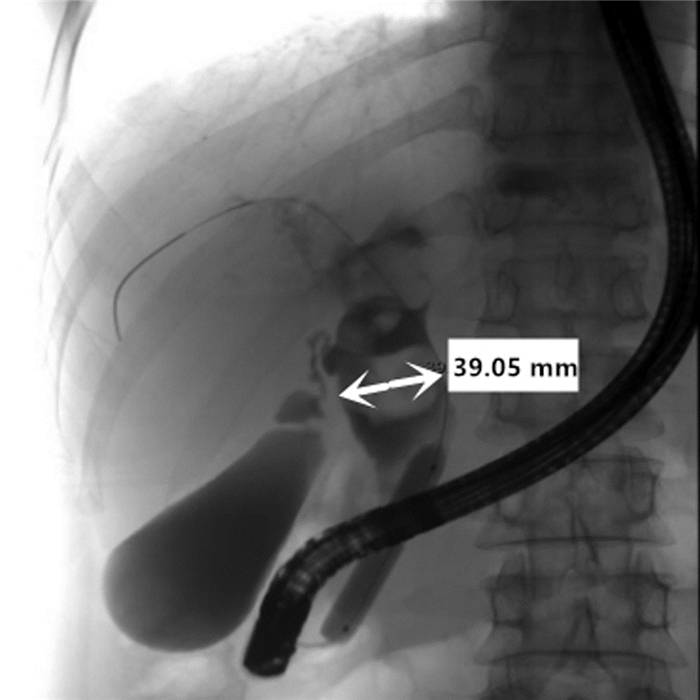

Primary fibrosarcoma of the liver misdiagnosed as hepatic abscess: A case report

Liuyang ZHU, Jiancun HOU, Long YANG, Wen TONG, Yamin ZHANG

2021, 37(7): 1665-1667. DOI: 10.3969/j.issn.1001-5256.2021.07.037

Abstract(696) HTML (210) PDF (3350KB)(42)

Abstract: